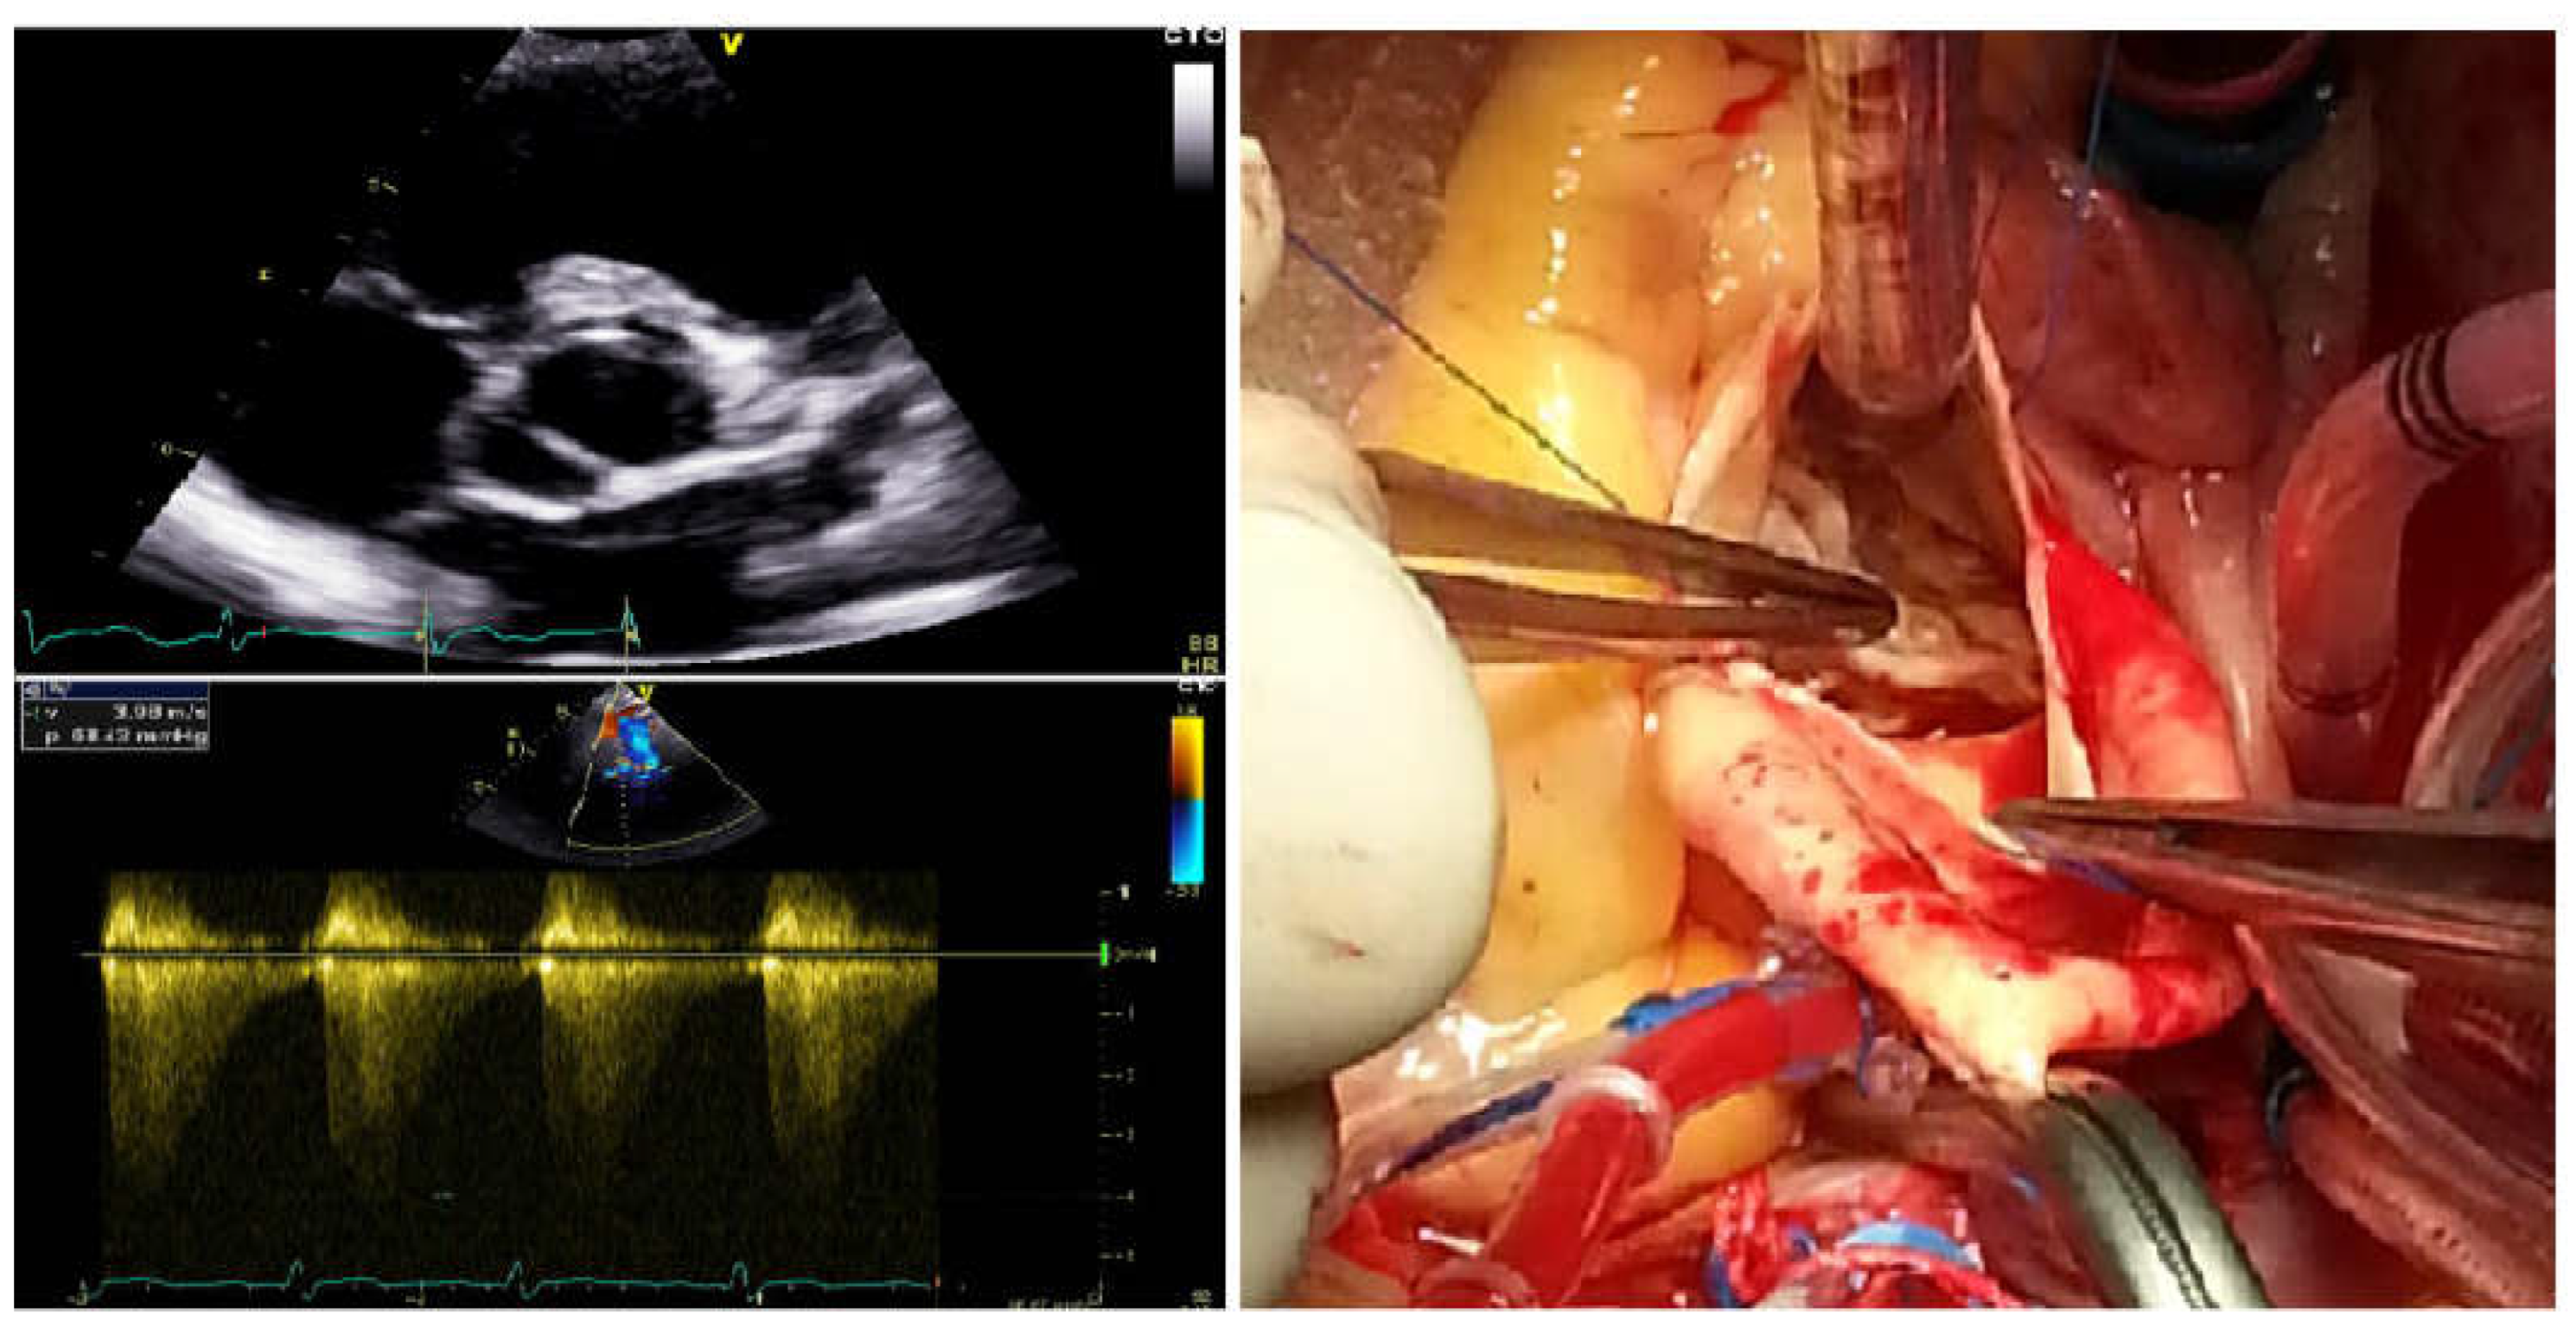

3.1. Clinical Characteristics of the Study Pedigree with BAV